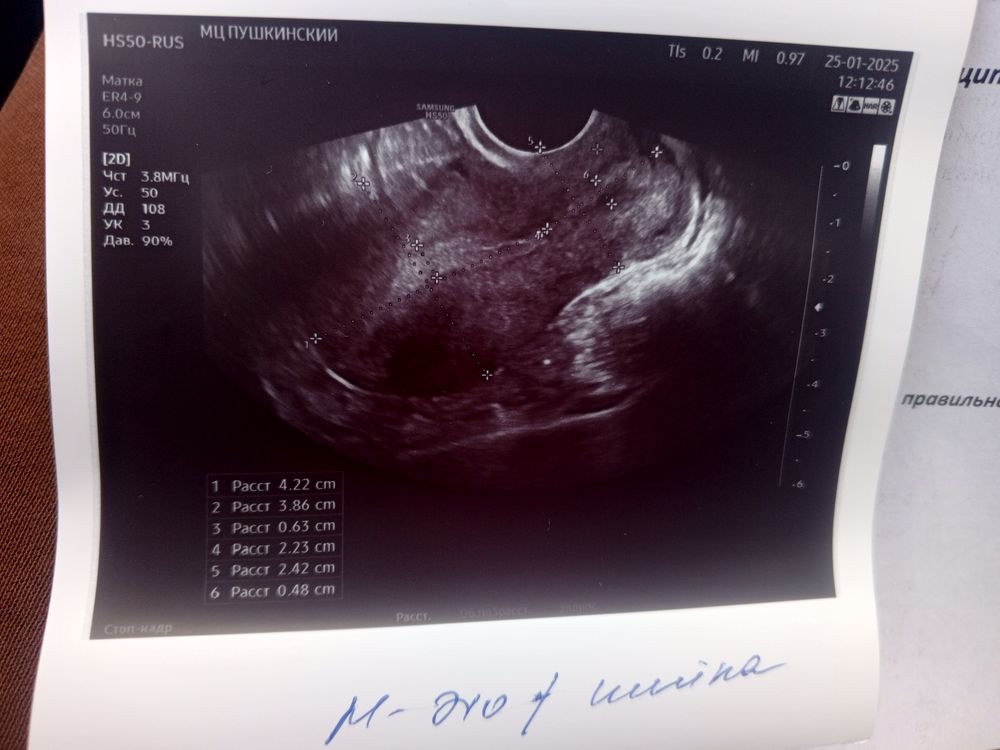

Какая фаза по узи?

Повышенная эхогенность у эндометрия наблюдается во вторую фазу, а фото нет?

Аня, Изображение Изображение Изображение

Светлана , вот смотрите первая и вторая фаза, мне кажется у вас не было овуляции и эндометрий на 1 фазу, т.к. видно линию смыкания, но я не узист конечно, просто уже за кучу узи у себя различаю Изображение Изображение

Аня, спасибо, значит могу считать что это месячные были, может эндометрий в прошлом цикле тонкий был то что такие скудные)) просто напугало что повышенной эхогенности, до этого она обычно писала по другому, ниже с позапрошлого цикла фолликулометрия... А из за чего эхогенность повышенная может быть? Я просто сейчас болею сильно, пью антибиотик, может из-за этого? Гормональное ни чего не пью

Светлана , неоднородность и повышенная эхогенность может и изза хронического эндометрита быть, например. Надо это с врачем обсуждать и смотреть в следующем цикле как будет

Аня, вот сколько делаю узи, впервые что бы после месячных так было... (

Аня, вот это как я понимаю эндометрий или нет? Изображение